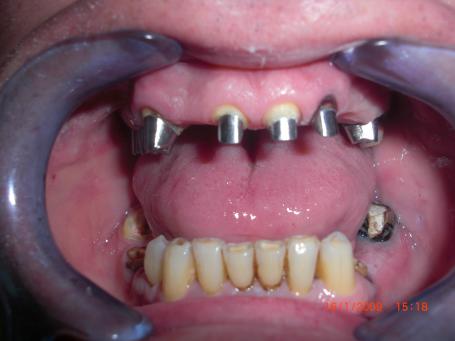

3°)Pose des Inlays cores

Après la réalisation des soins dentaires, des dévitalisations dentaires et enregistrement de l'occlusion une empreinte est réalisée pour réaliser les pivots dentaires.